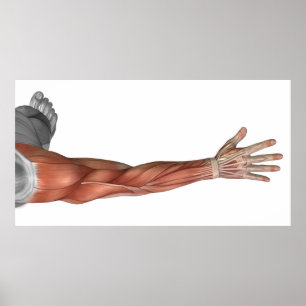

Affiche Anatomie Musculaire Du Bras Humain, Vue Postérieur

Prix153,00 €